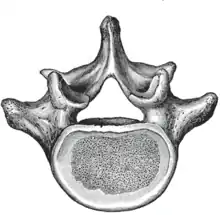

The adjacent figure depicts the general characteristics of the first through fourth lumbar vertebrae. The fifth vertebra contains certain peculiarities, which are detailed below.

As with other vertebrae, each lumbar vertebra consists of a vertebral body and a vertebral arch. The vertebral arch, consisting of a pair of pedicles and a pair of laminae, encloses the vertebral foramen (opening) and supports seven processes.

Body

The vertebral body of each lumbar vertebra is kidney shaped, wider from side to side than from front to back, and a little thicker in front than in back. It is flattened or slightly concave above and below, concave behind, and deeply constricted in front and at the sides.[1]

Arch

The pedicles are very strong, directed backward from the upper part of the vertebral body; consequently, the inferior vertebral notches are of considerable depth.[1] The pedicles change in morphology from the upper lumbar to the lower lumbar. They increase in sagittal width from 9 mm to up to 18 mm at L5. They increase in angulation in the axial plane from 10 degrees to 20 degrees by L5. The pedicle is sometimes used as a portal of entrance into the vertebral body for fixation with pedicle screws or for placement of bone cement as with kyphoplasty or vertebroplasty.

The laminae are broad, short, and strong.[1] They form the posterior portion of the vertebral arch. In the upper lumbar region the lamina are taller than wide but in the lower lumbar vertebra the lamina are wider than tall. The lamina connects the spinous process to the pedicles.

The vertebral foramen within the arch is triangular, larger than the thoracic vertebrae, but smaller than in the cervical vertebrae.[1]

Processes

The spinous process is thick, broad, and somewhat quadrilateral; it projects backward and ends in a rough, uneven border, thickest below where it is occasionally notched.[1]

The superior and inferior articular processes are well-defined, projecting respectively upward and downward from the junctions of pedicles and laminae. The facets on the superior processes are concave, and look backward and medialward; those on the inferior are convex, and are directed forward and lateralward. The former are wider apart than the latter since in the articulated column, the inferior articular processes are embraced by the superior processes of the subjacent vertebra.[1]

The transverse processes are long and slender. They are horizontal in the upper three lumbar vertebrae and incline a little upward in the lower two. In the upper three vertebrae they arise from the junctions of the pedicles and laminae, but in the lower two they are set farther forward and spring from the pedicles and posterior parts of the vertebral bodies. They are situated in front of the articular processes instead of behind them as in the thoracic vertebrae, and are homologous with the ribs.[1]